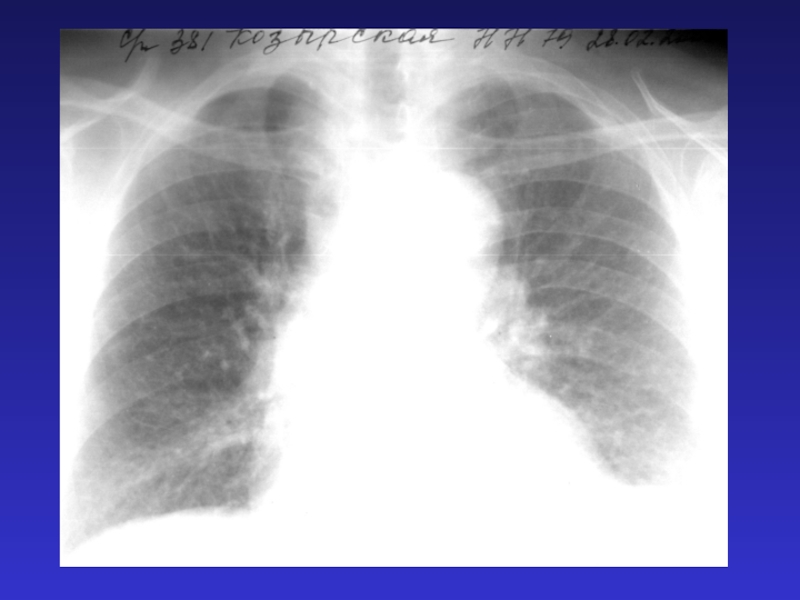

Слайд 31Туберкулез хр. диссеминированный

Туберкулез хр. диссеминированный